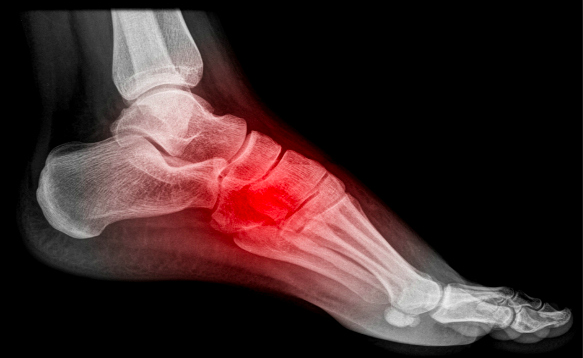

Stress Fractures

Stress fractures are small, hairline cracks within a bone. Unlike standard fractures which typically occur from trauma or injury, stress fractures develop over time through repetitive stress to a bone. While stress fractures can affect any bone, they are more common in bones such as the metatarsals (the long bones of the feet) and the tibia (shin bone).